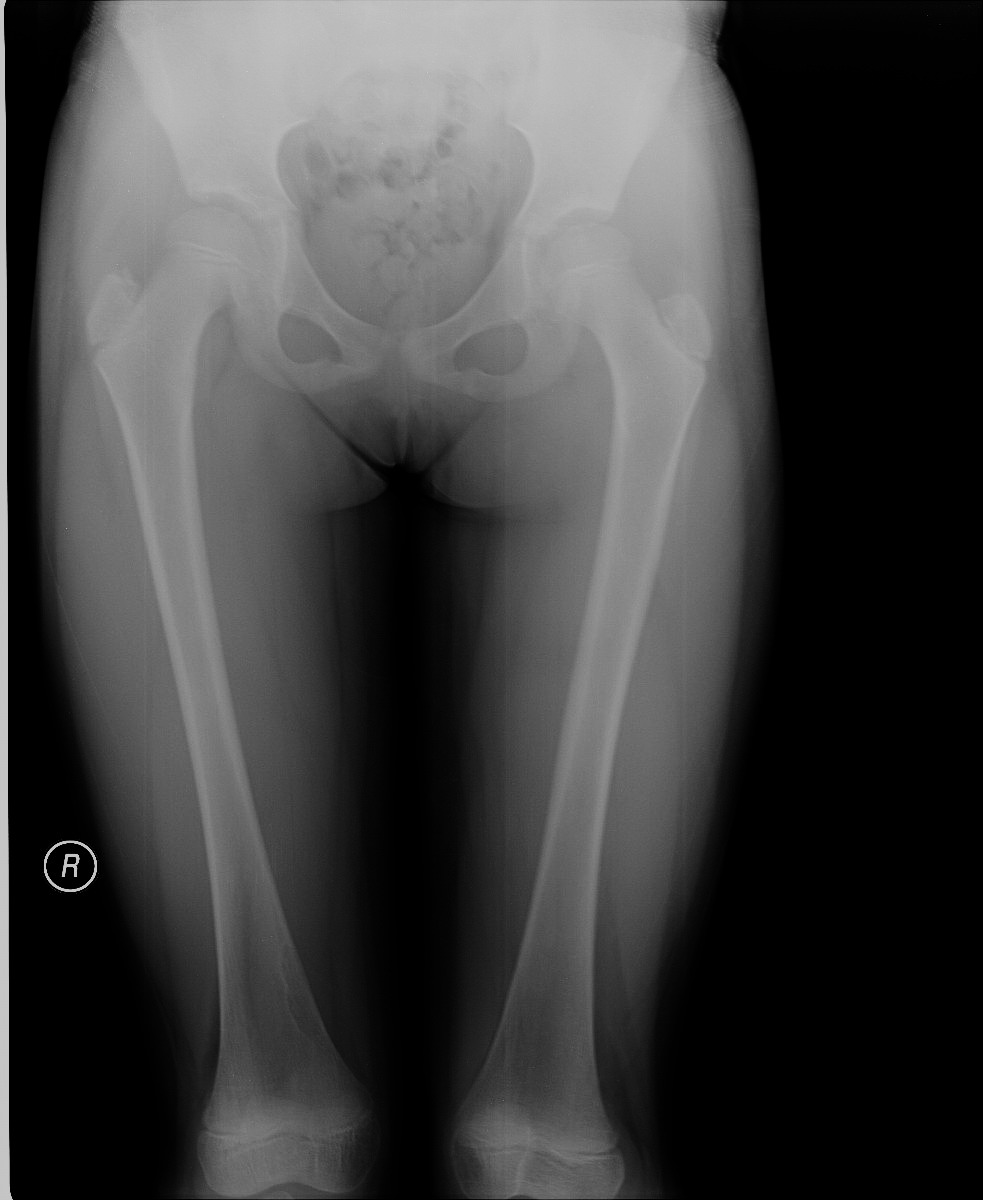

标题: X5349:女,8岁,外伤就诊。右股骨下段内侧皮质下低密度影

女,8岁,外伤就诊。右股骨下段内侧皮质下低密度影考虑什么?图像不太清楚,请大家原谅!